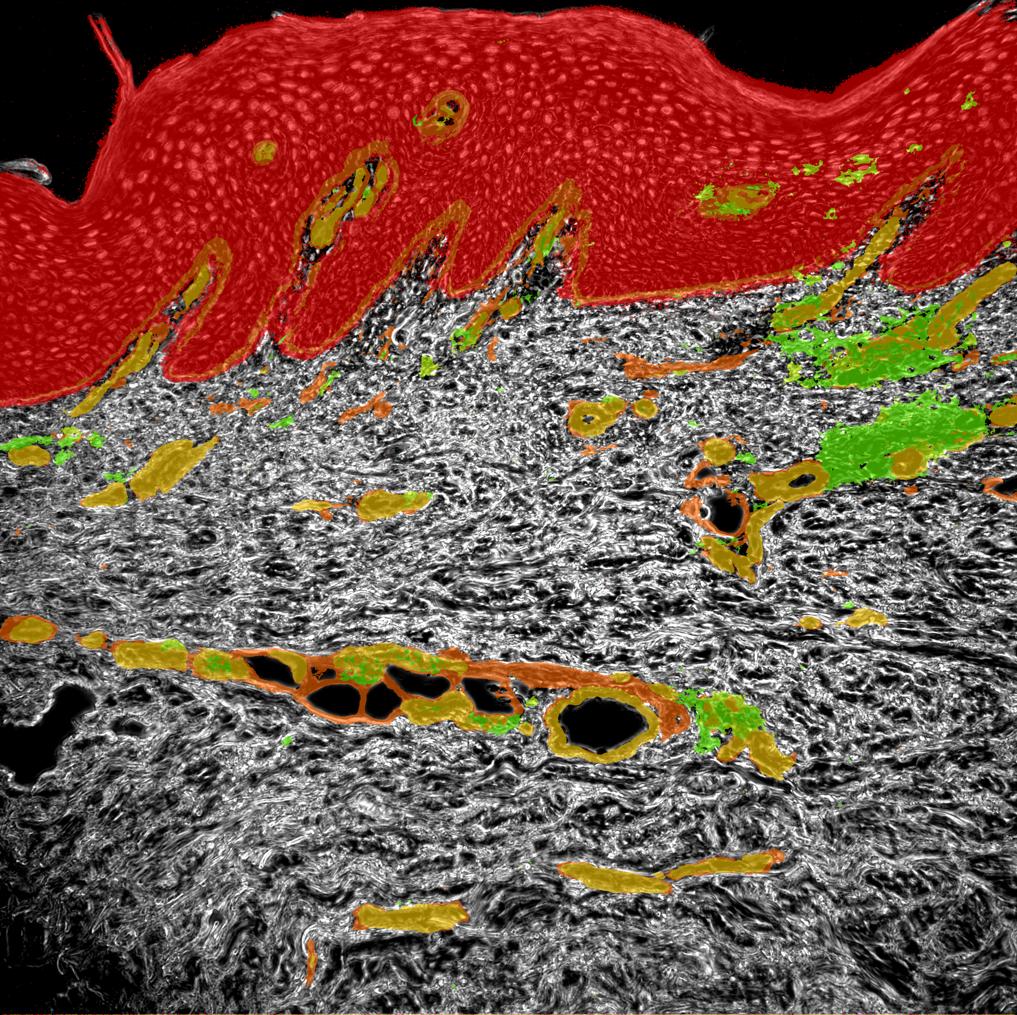

Phase contrast image

Keratinocytes

Collagen

Vessels

CD3 T cells

Psoriatic Skin

Human tissue section

Autoimmune loop